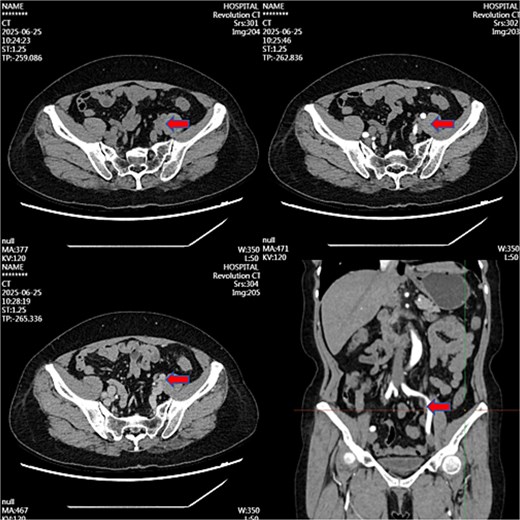

Month 36: Near-complete resolution (Fig. 3).

Contrast-enhanced CT image at 36-month follow-up demonstrating near-complete resolution of previously described left iliac vessel mass following medical therapy.